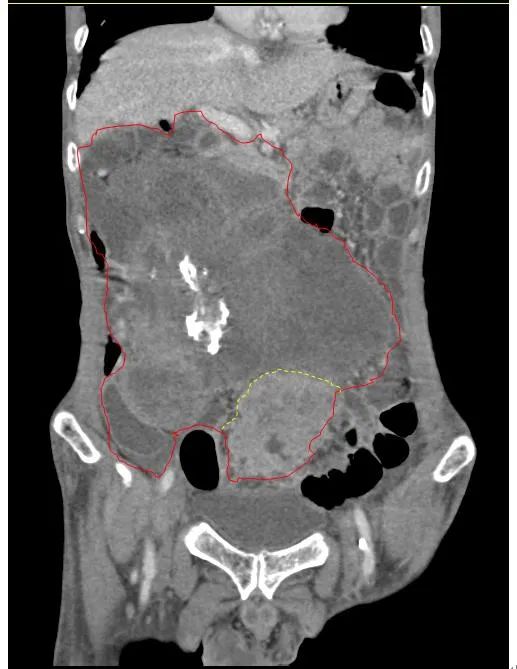

患者王大爺,男,72歲,發(fā)現(xiàn)腹腔腫物10余年,近兩年來(lái)患者雙下肢乏力、貧血,依靠間斷輸血維持著正常生活,出現(xiàn)頭昏,行動(dòng)困難,腹部疼痛及便血慕名來(lái)我院就診。入院后查體評(píng)估患者年齡大,體質(zhì)差,嚴(yán)重貧血,肺部感染及腸梗阻征象,腹部增強(qiáng)CT檢查提示腹膜后巨大腫瘤,長(zhǎng)徑超過(guò)30厘米,占據(jù)大部分腹腔,并可能存在雙原發(fā)腫瘤。

苗滿園腫瘤外科團(tuán)隊(duì)在麻醉科/手術(shù)室的緊密配合下為該患者進(jìn)行手術(shù),術(shù)中發(fā)現(xiàn)腫瘤巨大,幾乎占據(jù)了整個(gè)腹腔,從左側(cè)向右腹腔延伸,向上將肝、腎擠向膈下,向左將胃及小腸擠向左上腹,向下深達(dá)盆腔內(nèi),包繞下腔靜脈、腸系膜上動(dòng)脈等大血管及輸尿管,回盲部及回腸也受侵犯。手術(shù)難度巨大,風(fēng)險(xiǎn)極高。團(tuán)隊(duì)?wèi){借著高超的手術(shù)技能和精準(zhǔn)的手術(shù)預(yù)案沉著應(yīng)對(duì),迎難而上,應(yīng)用高頻電刀、超聲刀、切割縫合器等先進(jìn)設(shè)備,耗時(shí)近5小時(shí)為患者切除了巨大腹腔腫瘤,并聯(lián)合右半結(jié)腸切除,術(shù)中出血僅50ml。術(shù)后病理為腹膜后巨大平滑肌瘤+回腸腺癌。